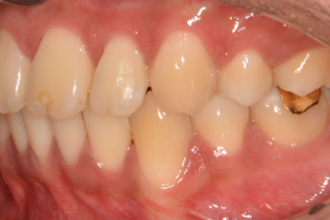

치아교정

굿프렌즈 치과 임상 케이스

직접 확인해보세요!